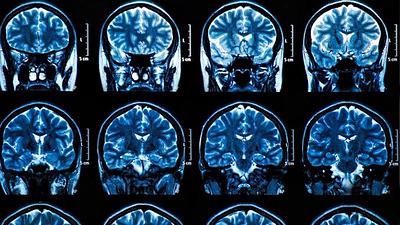

Estudo sugere relação entre bactéria da gengiva e Alzheimer

Cientistas acreditam ter descoberto possível causa da doença neurodegenerativa que é um dos maiores mistérios da medicina. Primeiros testes mostram resultados positivos, inclusive de reparação de neurônios danificados.